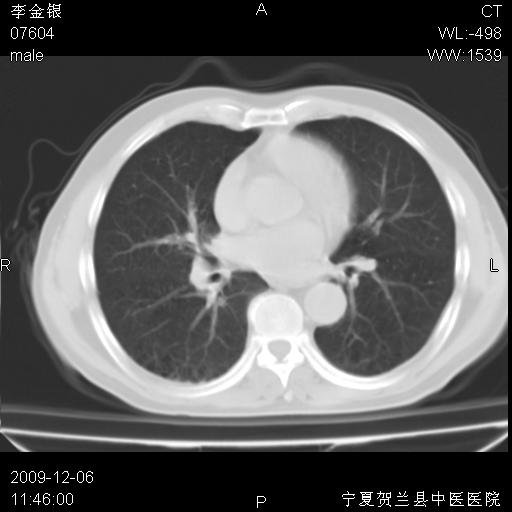

该病人 ,男,62岁,主因咳痰带血两天

考虑右肺中央型占位性病变并阻塞性肺炎.(右肺上叶支气管变窄),建议支纤镜检查.

考虑右肺中心型肺癌伴阻塞性肺炎及右肺门淋巴结转移,建议纤维支气管镜进一步检查。

支气管壁明显增厚 管腔狭窄,腔静脉后多个淋巴肿大,结合年龄病史考虑右肺上叶中央型肺癌并阻塞性肺炎

右肺上叶后段支气管阻塞,右上肺门占位,相应肺段阻塞性肺炎,右肺门有淋巴结肿大。诊断右肺上叶中心型肺癌,阻塞性肺肺炎、右肺门淋巴结转移。

右上叶支气管狭窄,管壁增厚,远端斑片状软组织影,病灶邻近叶间裂,叶间裂无移位。

诊断右肺中央型肺癌。

那个片影应该大部分都是病灶,病灶沿肺段支气管分支生长,后段完全显示不清、闭塞。若为不张应该伴有叶裂的移位,若为炎症应有空气支气管征。

考虑右侧中央型肺癌伴右肺上叶后段阻塞性炎症、肺不张、右肺门和纵隔淋巴结肿大。

右肺上叶中心型肺癌,阻塞性肺炎、右肺门和纵隔淋巴结转移。